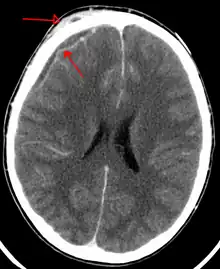

An abscess that has led to an intracranial subdural empyema as seen on CT | |

Subdural empyema is a form of empyema – a collection of pus, in the subdural space.

Bacterial or occasionally fungal infection of the skull bones or air sinuses can spread to the subdural space, producing a subdural empyema. The underlying arachnoid and subarachnoid spaces are usually unaffected, but a large subdural empyema may produce a mass effect. Further, a thrombophlebitis may develop in the bridging veins that cross the subdural space, resulting in venous occlusion and infarction of the brain. With treatment, including surgical drainage, resolution of the empyema occurs from the dural side, and, if it is complete, a thickened dura may be the only residual finding. Symptoms include those referable to the source of the infection. In addition, most patients are febrile, with headache and neck stiffness, and, if untreated, may develop focal neurologic signs, lethargy, and coma. The CSF profile is similar to that seen in brain abscesses, because both are parameningeal infectious processes. If diagnosis and treatment are prompt, complete recovery is usual.